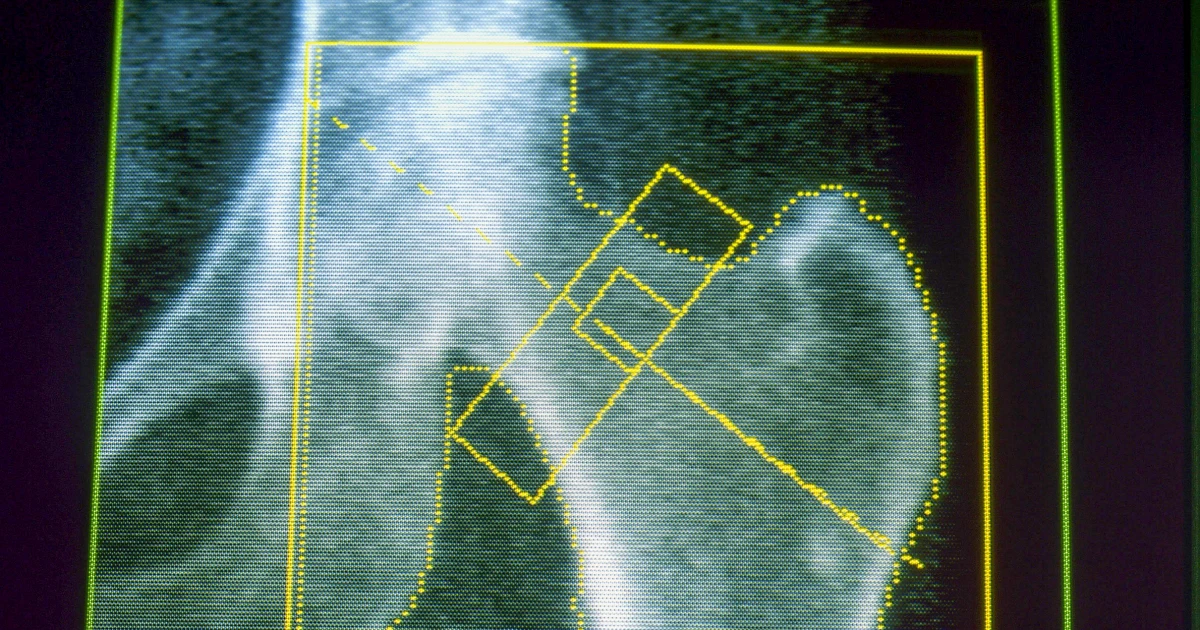

Osteoporosis is a disease that weakens the bones and makes them likelier to break or fracture, often from minor falls. It’s a common concern for many older adults and for people who lose a significant amount of weight over a short period of time. Gout, meanwhile, is a painful form of arthritis that can occur when the body has too much uric acid, which can come from a diet high in red meat and alcohol — as well as rapid weight loss.

About 4% of GLP-1 users developed osteoporosis, compared with a little over 3% of nonusers — an increased risk of about 30%. A related condition, osteomalacia, which involves the softening of the bones, was rare but also occurred about twice as often among people on GLP-1s.